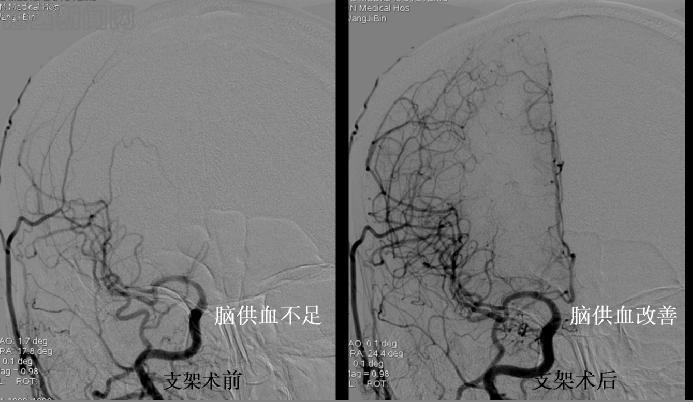

病例2 张某某,男,63岁,突发左侧肢体瘫痪入院,既往有吸烟和高血压病史,MRI检查发现右侧大面积脑梗死,全脑血管造影(DSA)发现右侧颈内动脉重度狭窄,脑供血明显不足,患者同意后在局麻下行颈动脉支架置入术,术后即刻造影显示颈动脉狭窄解除,血流恢复通畅,脑供血不足明显改善。患者术后瘫痪症状明显改善,第4天出院。术后随访1年8月,CT血管造影(CTA)显示支架通畅,患者独立行走。